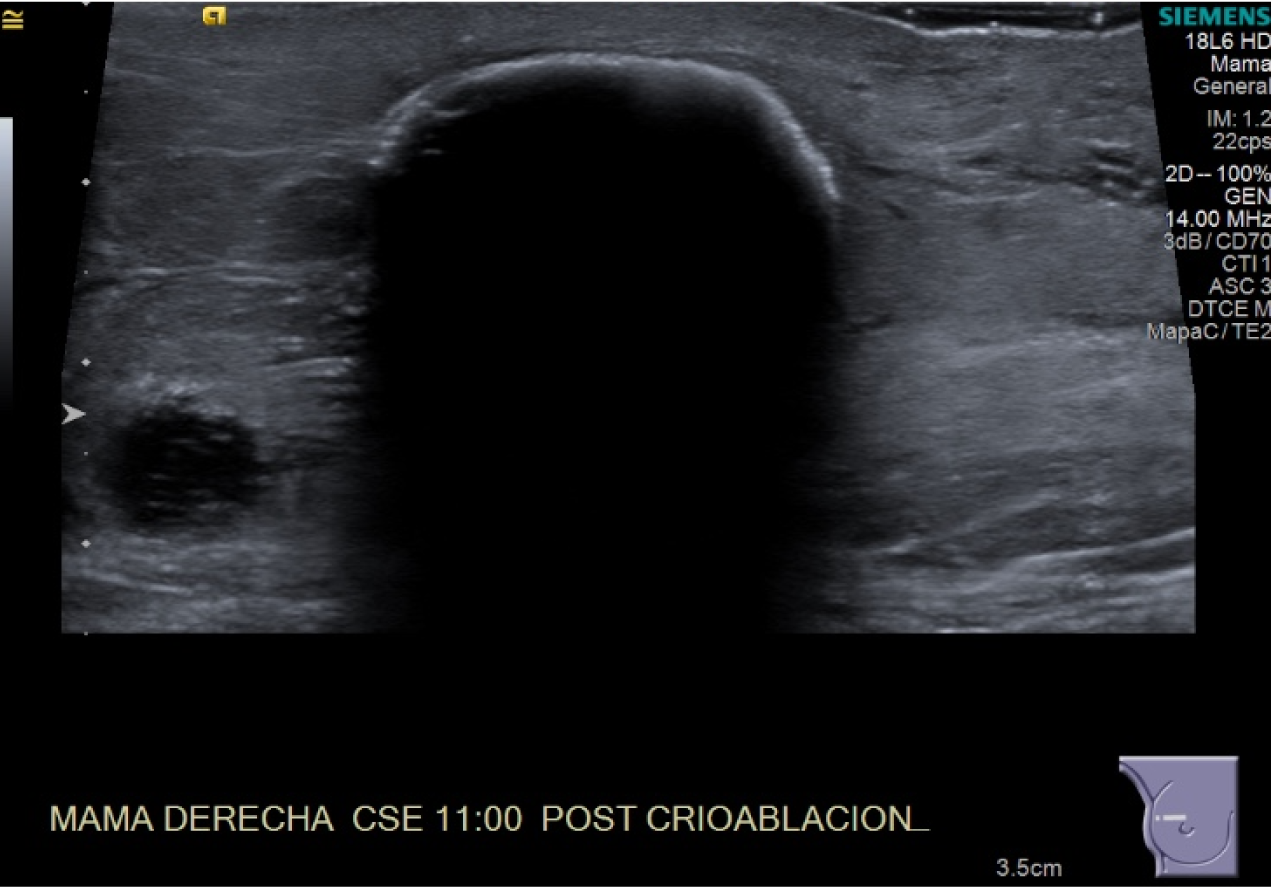

Crioablacion de tumor en mama derecha